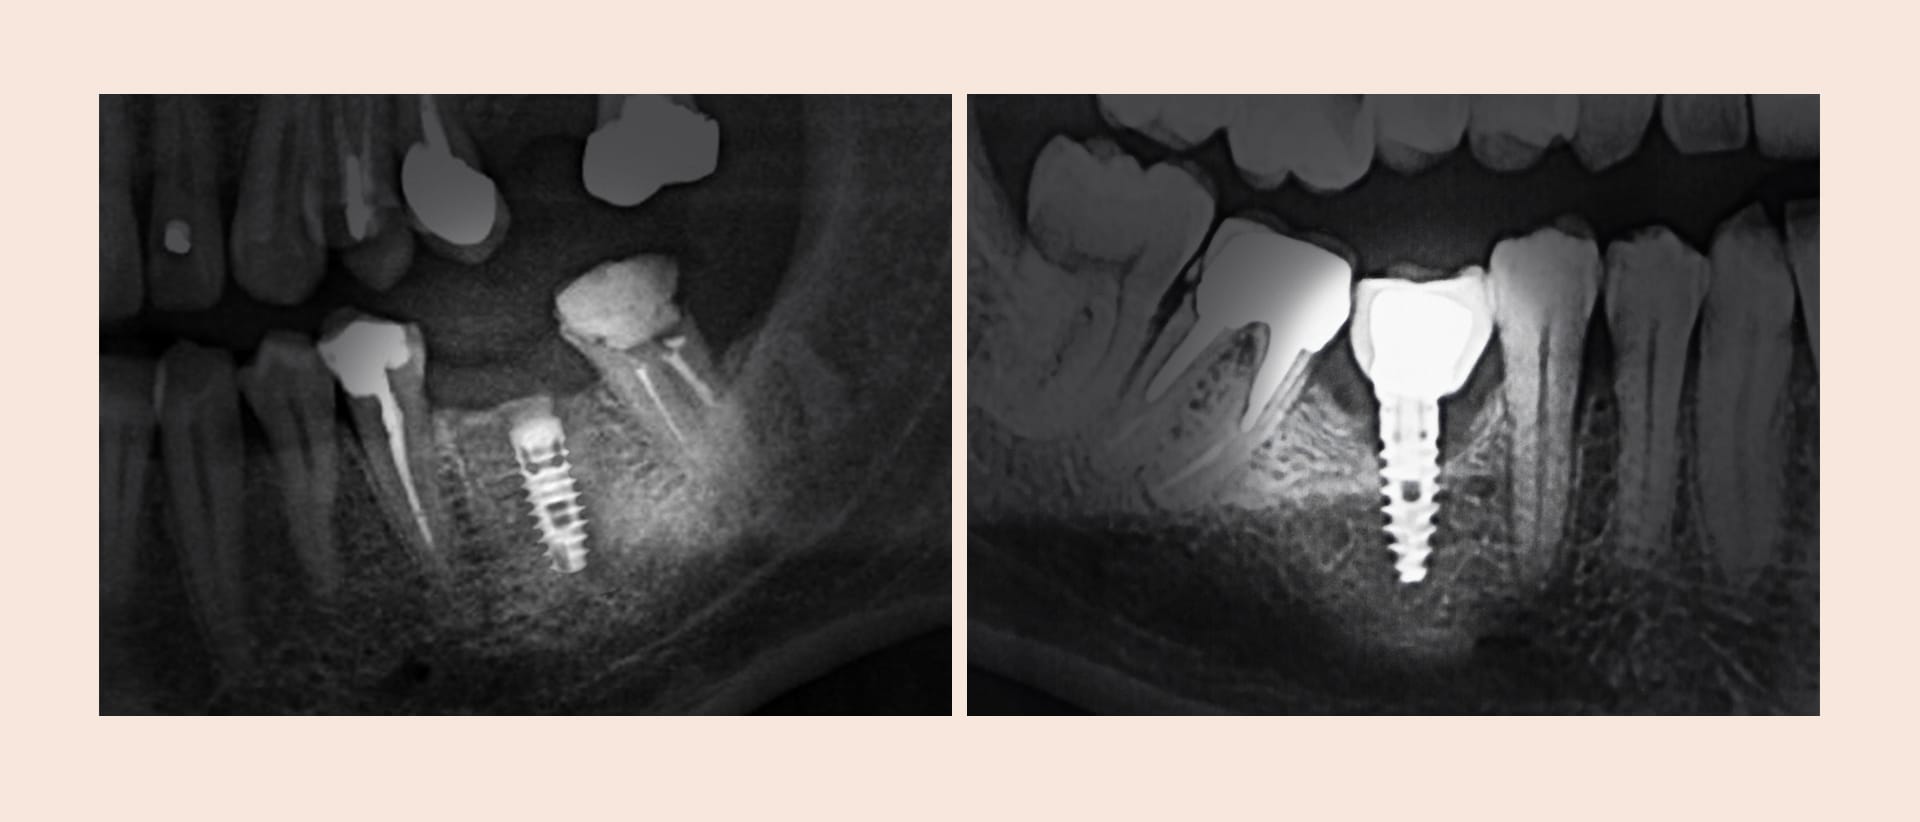

- レントゲンでインプラント周囲の骨欠損が確認されます。

| 精密診断 | 3D CTなどのデジタル機器で、損傷の程度、骨吸収の範囲、炎症の広がりを詳細に分析します。 |